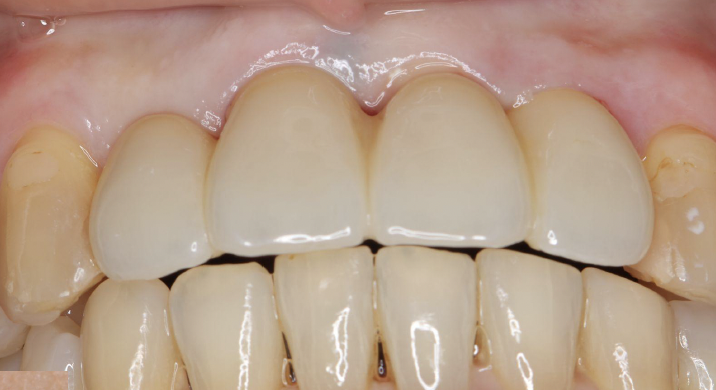

歯周病による前歯部抜歯即時インプラント症例(50代女性)

手術直後、1週間後の抜糸時、3か月後の写真です。

抜歯、インプラント埋入から6か月後に完成しました。